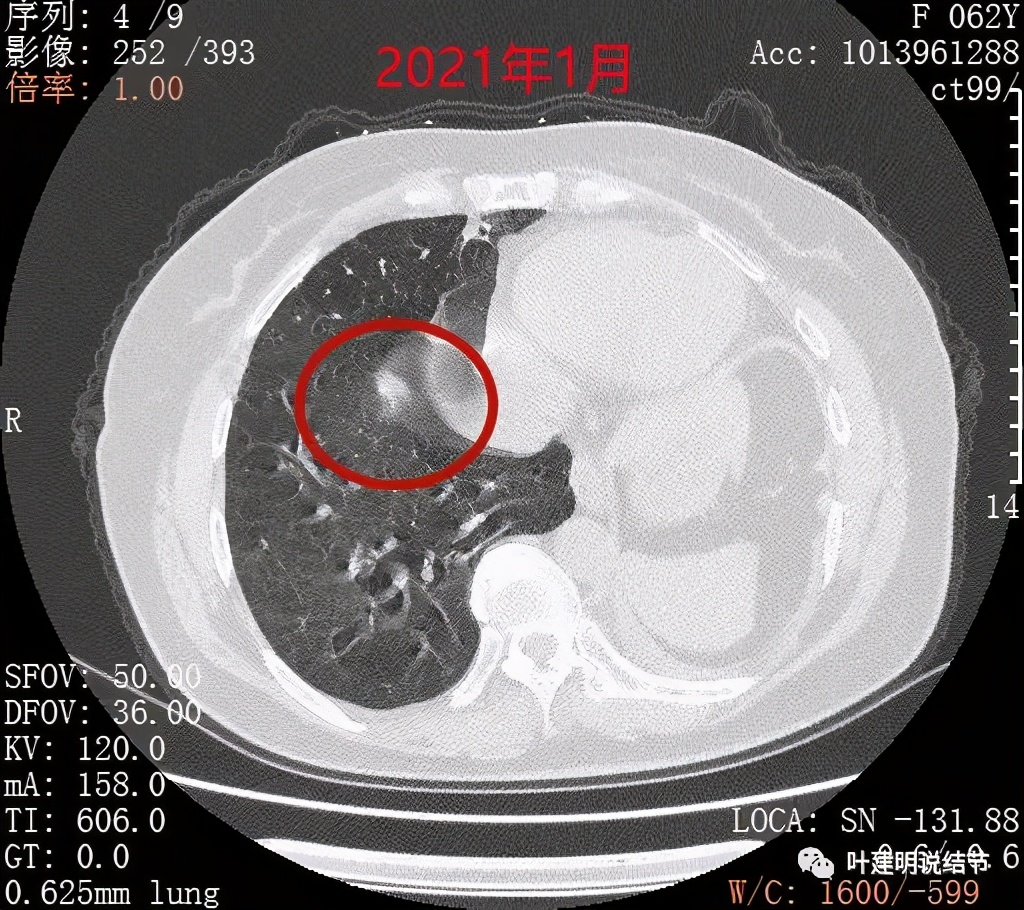

近日某A来复查,见右下叶结节较前有所增大进展。某A告诉我,2年多前已经告诉她右下结节也可能是恶性的,但特征还不够典型,需以后随访对比。另外即使恶性,也要拉长两肺手术的间隔才有可能切除,否则肺功能也无法耐受再次手术。这我倒真有些记不清当时具体的*法讲**了呢。我们先来比较下右下肺这结节每次复查时的对比:

前次手术时右下结节偏实性,不太致密,边缘显模糊,还不能认定为恶性,但需随访观察对比

到了一年后,这结节没有吸收好转,反而边上较前清楚了一点起来,仍像磨玻璃过渡到实性的阶段(偏实性,但又不是很密实)

到了今年1月份时,结节还在,瘤肺边界似较前清楚了点